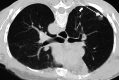

Image-guided percutaneous lung ablation has proven to be a valid treatment alternative in patients with early-stage non-small cell lung carcinoma or oligometastatic lung disease. Available ablative modalities include radiofrequency ablation, microwave ablation, and cryoablation. Currently, there are no sufficiently representative studies to determine significant differences between the results of these techniques. However, a common feature among them is their excellent tolerance with very few complications. For optimal treatment, radiologists must carefully select the patients to be treated, perform a refined ablative technique, and have a detailed knowledge of the radiological features following lung ablation. Although no randomized studies comparing image-guided percutaneous lung ablation with surgery or stereotactic radiation therapy are available, the current literature demonstrates equivalent survival rates. This review will discuss image-guided percutaneous lung ablation features, including available modalities, approved indications, possible complications, published results, and future applications.